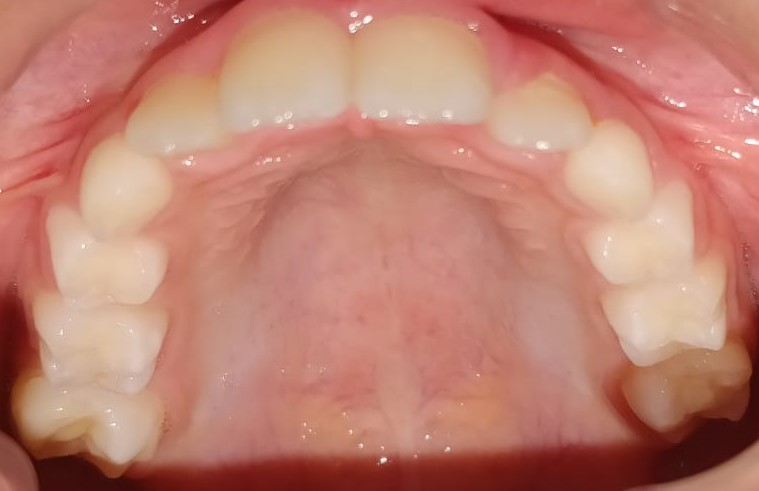

88) Haiqa maryam – severe upper arch crowding and Bolton discrepancy